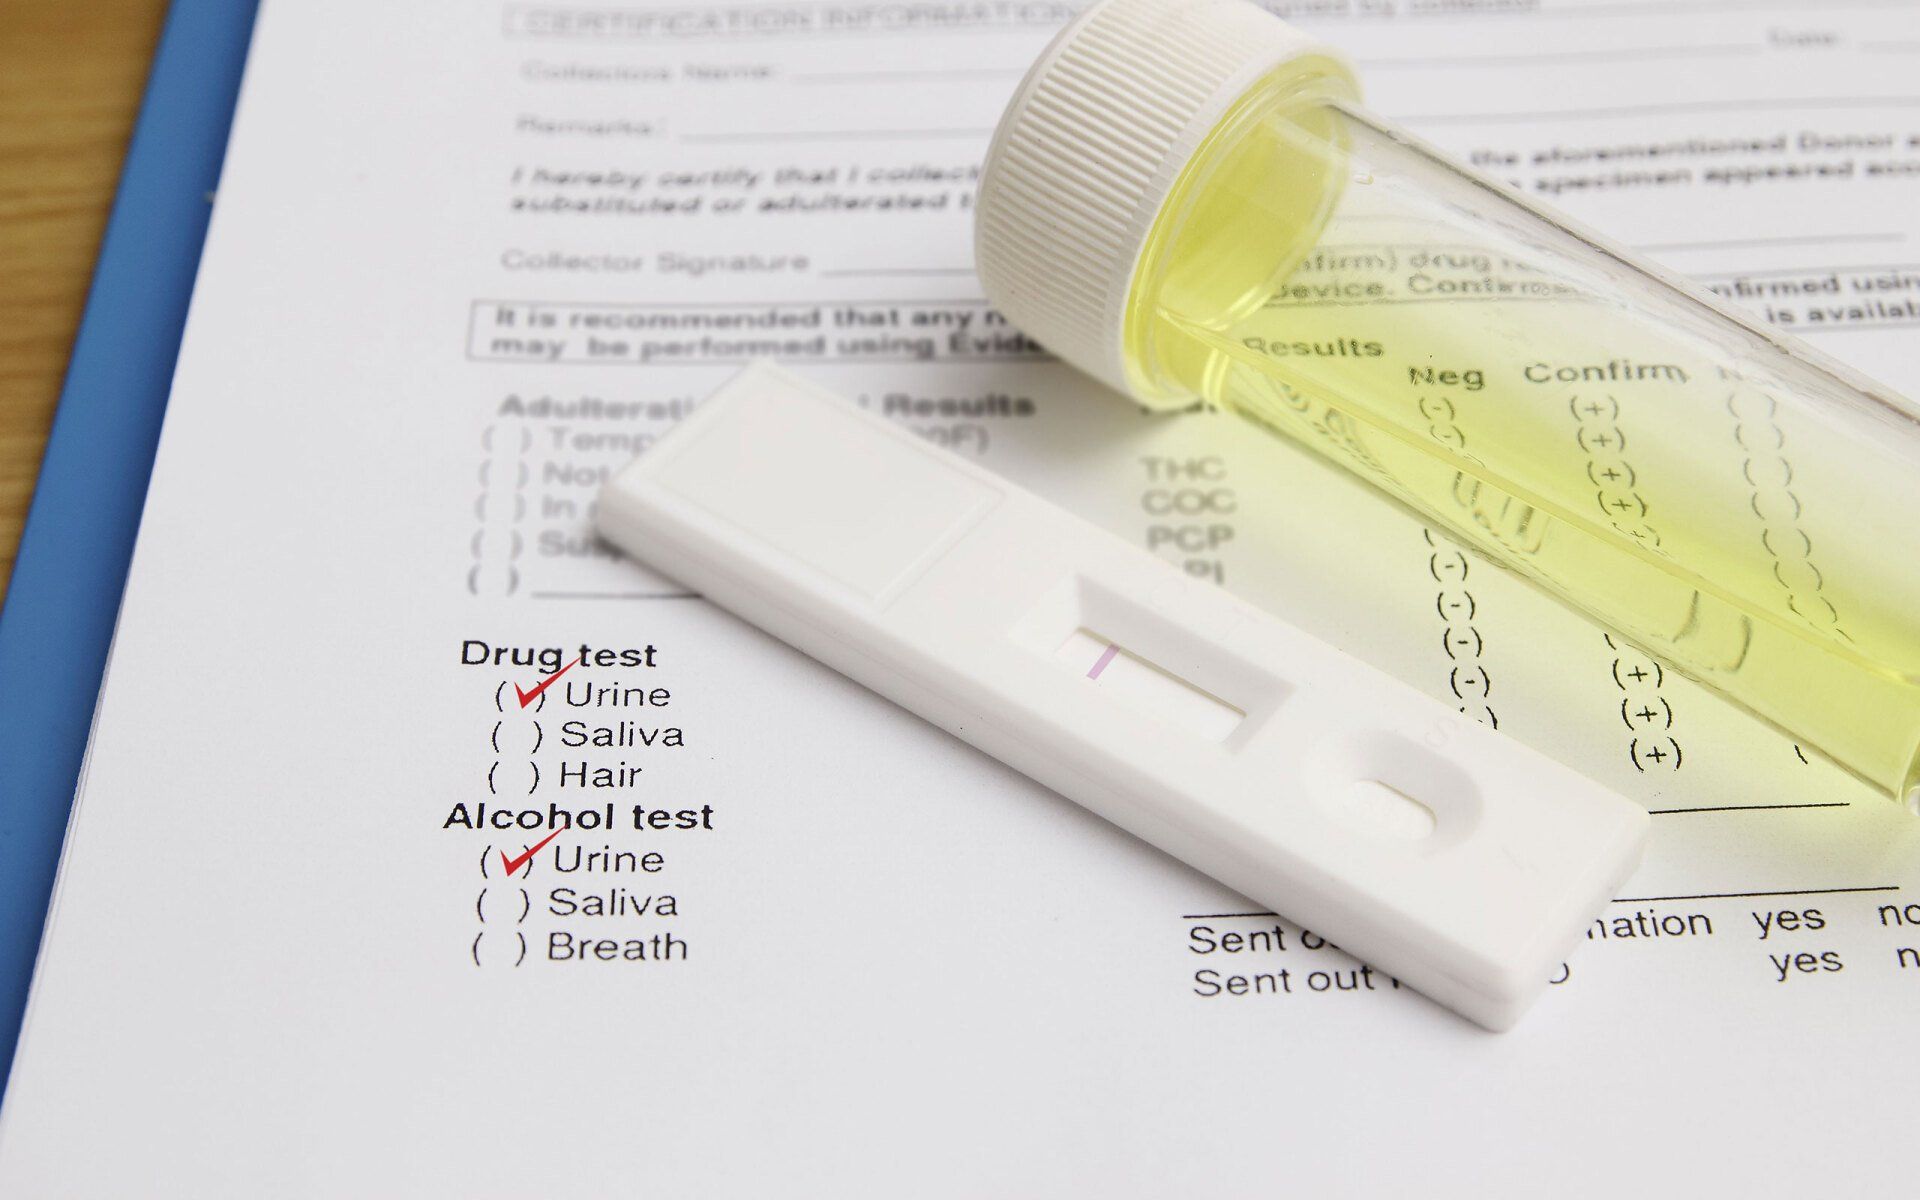

Occupational Medical Services

If you've been injured at work, let us help you. We are focused on the treatment of work-related injuries and illnesses. Call us.